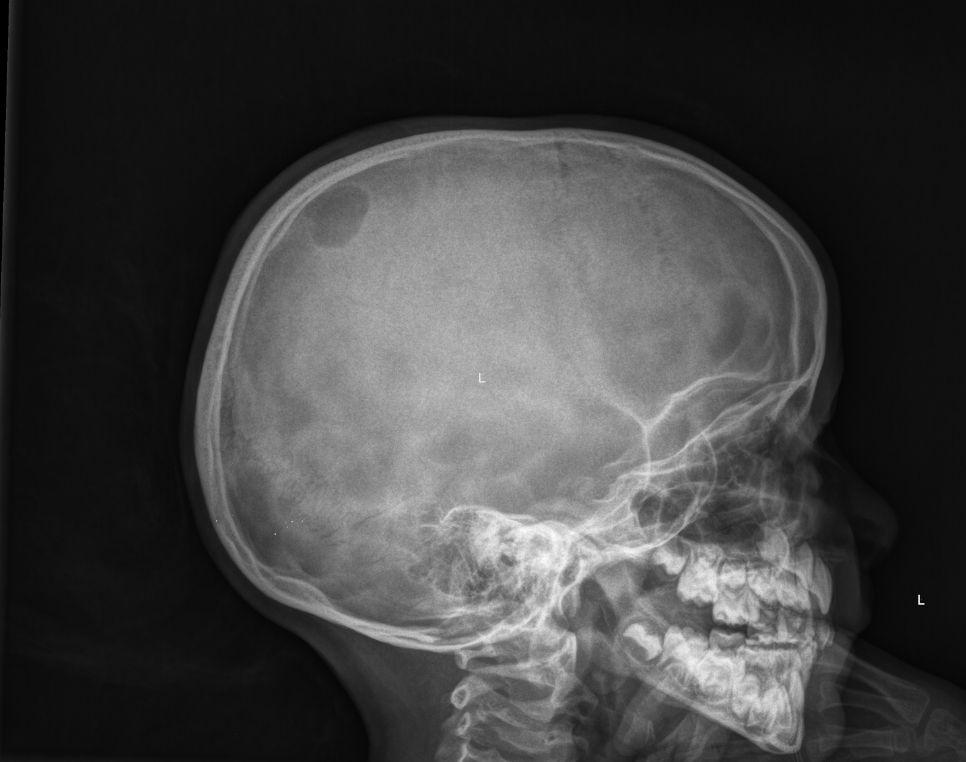

Een 6-jarig meisje van Marokkaanse afkomst kwam met haar ouders op de afdeling Spoedeisende Hulp (SEH) in verband met een zwelling op haar hoofd die mogelijk was ontstaan na een trauma. Bij neurologisch onderzoek vonden we geen afwijkingen. Bij lichamelijk onderzoek voelden we links pariëtaal op de schedel een niet-pijnlijke, fluctuerende zwelling met een diameter van 4 cm. De zwelling was niet afwijkend van kleur en er was geen uitvloed. Langs de rand van de zwelling leek een opstaand randje bot palpabel te zijn, het bot was palpatoir intact.